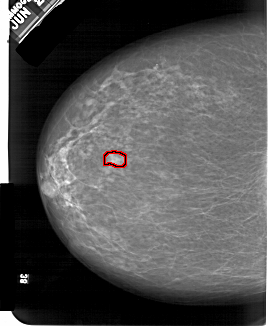

FILE: A_1554_1.LEFT_CC.OVERLAY

TOTAL_ABNORMALITIES 1

ABNORMALITY 1

LESION_TYPE MASS SHAPE OVAL MARGINS OBSCURED

ASSESSMENT 4

SUBTLETY 4

PATHOLOGY BENIGN

TOTAL_OUTLINES 1

BOUNDARY